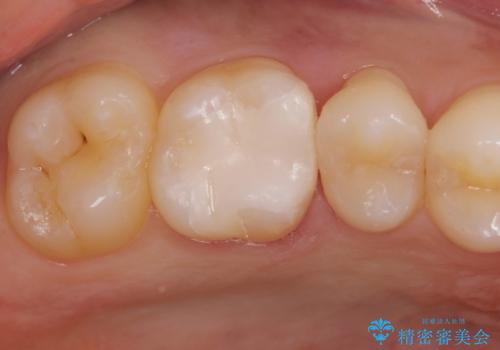

白くて適合の良い詰め物が入りました。

e-maxインレーは保険のインレーに比べて虫歯の再発のリスクが低くなります。